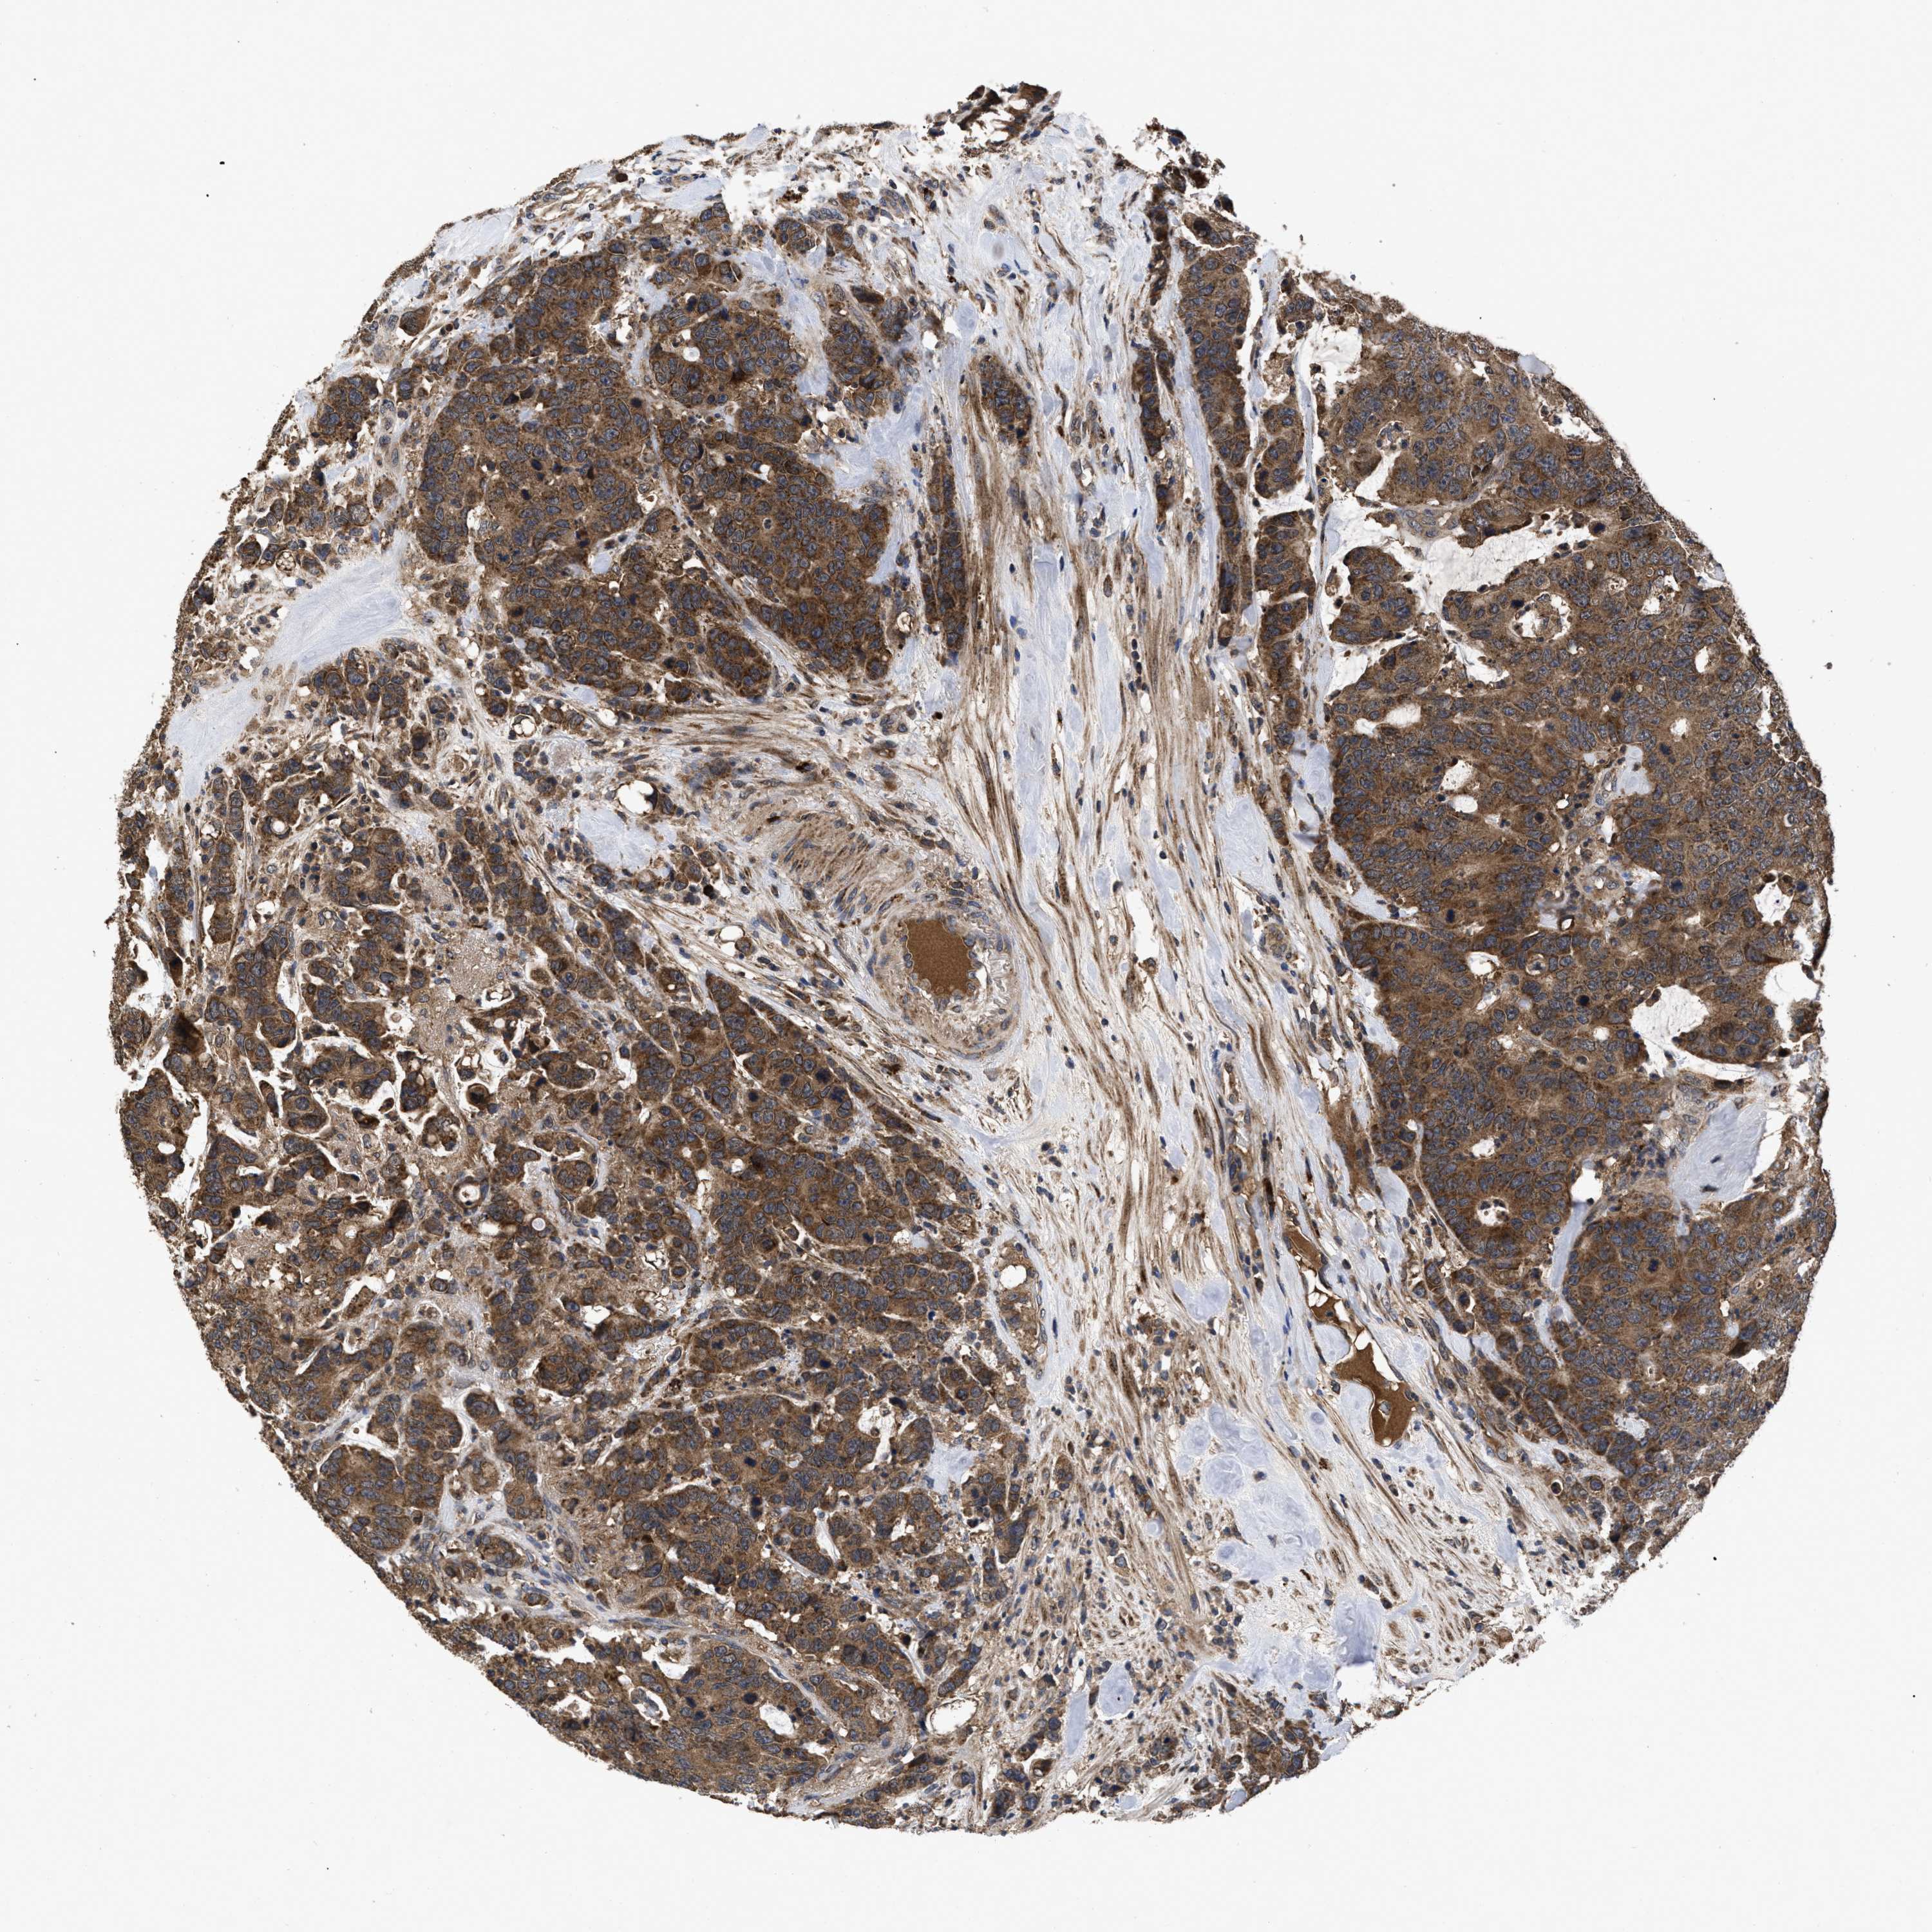

Colorectal cancer

Rectum adenocarcinoma